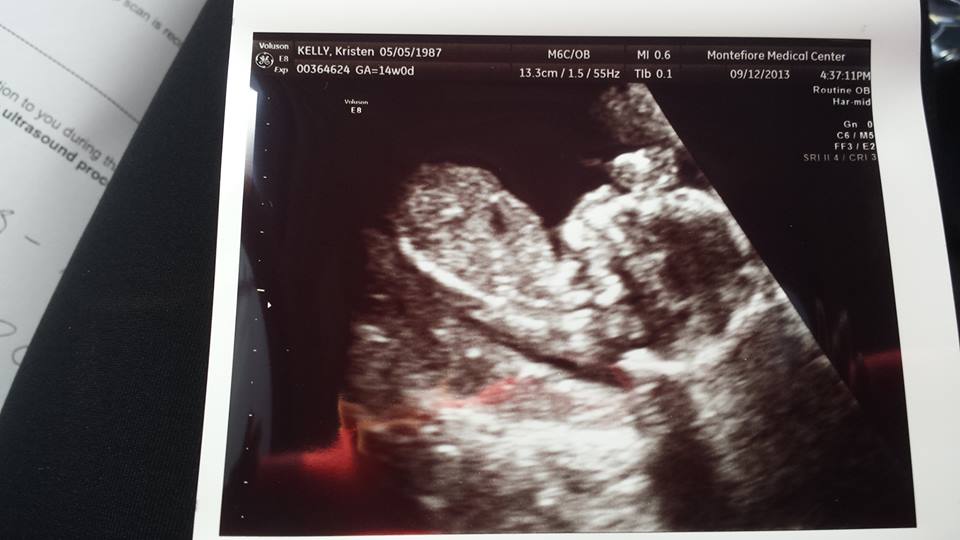

No nub on here - sorry x

Sorry no nub. Do you have another picture? X